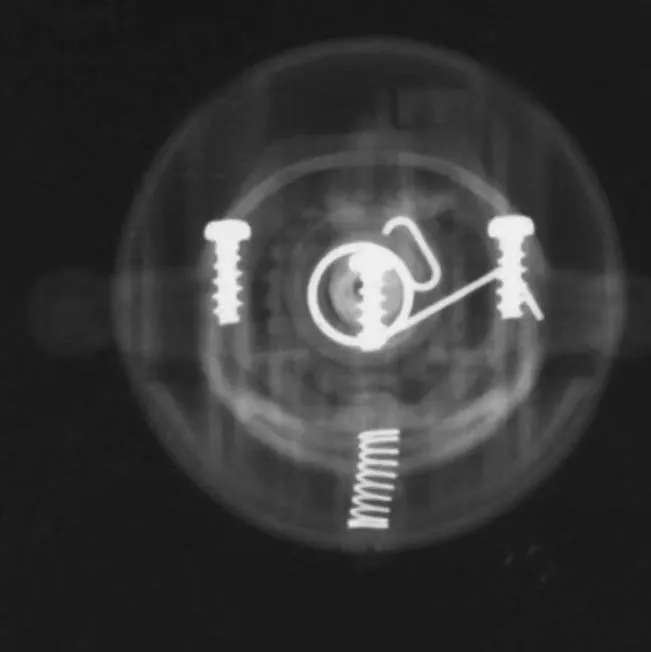

レントゲン撮影では骨、小石や金属はわかりやすいですが、ぬいぐるみやティッシュ、プラスチック等はかなり特殊な条件でないとわかりません。

写真は、ぬいぐるみとプラスチックのドラえもんのレントゲンです。金属ねじははっきりとわかりますが、ドラえもんの形など細部はぼんやりしており、写りにくいです。

【失敗】私の想定よりもぬいぐるみドラえもんが写ってしまいました。